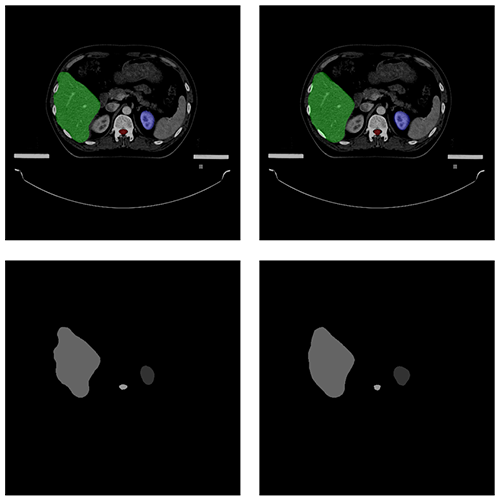

自動勾畫效果

AUTOMATIC CONTOURING

原圖

預測圖